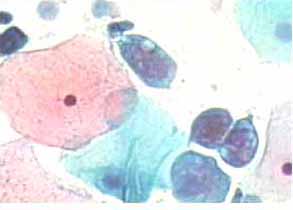

Τα διάμεσα κύτταρα εμφανίζονται στο επίχρισμα κατα Papanicoloau βασεόφιλα. Σχέση πυρήνα προς κυτταρόπλασμα 1:10: Δεξιά επιφανειακό κύτταρο, προς τα αριστερά, διάμεσα κύτταρα. Η οξεοφιλία σε δυο από αυτά οφείλεται σε εκφυλιστικές αλλοιώσεις